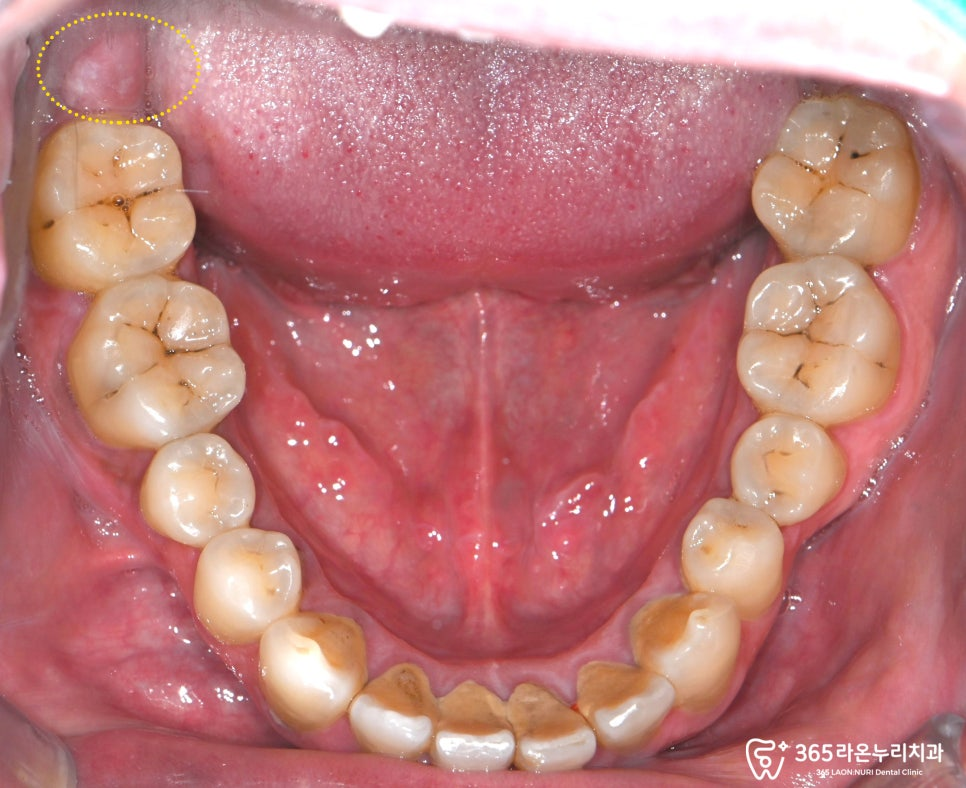

우선 구강 상태를 확인해보겠습니다.

현재, 오른쪽 맨 뒤 어금니쪽으로

잇몸 붓기가 심한 모습인데요.

붓기 가 나타난 원인으로

매복 사랑니 가 있는 것으로 의심되어,

구강을 자세히 확인해보기로 했습니다.